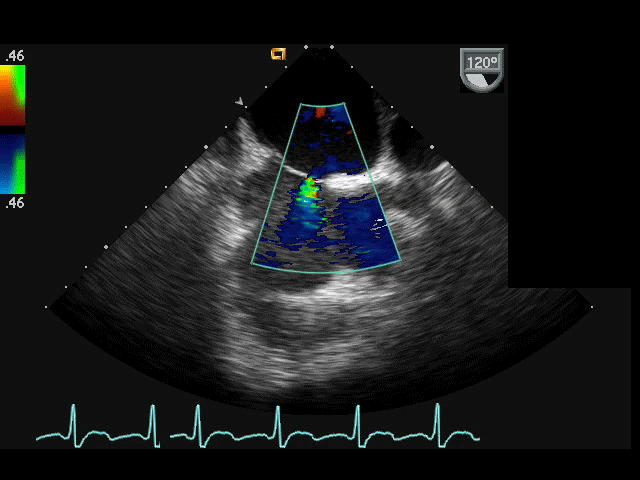

• Ещё одним важным инструментом диагностики является эхокардиография (сокращенно ЭхоКГ). С помощью ультразвукового обследования удаётся увидеть структуру сердца изнутри и выяснить возможные причины развития нарушений ритма.